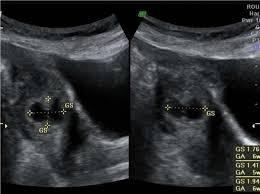

Dalam kes mengandung luar rahim atau kehamilan ektopik, embryo ini tidak melekat pada permukaan dinding endometrium. Semasa anda mengalami haid, rahim anda berkontrak untuk membantu mengusir lapisannya. Ketumbuhan pada dinding rahim atau fibroid. Kak, sshhh… jangan dulu donk. Apa yang lebih menakutkan lagi ialah tumbuhan kanser rahim atau pangkal rahim. Laporan wartawan grid.id, devi agustiana. Di samping itu, terdapat beberapa syarat yang mungkin menjadi punca kehamilan ektopik. Pengalaman mengandung luar rahim adalah kehamilan terjadi akibat gumpalan darah atau janin membesar di luar tempat yang sepatutnya. Adanya infeksi di daerah sekitar panggul. Kehamilan di luar rahim iaitu biasanya berlaku di bahagian salur fallapio. Antara kaedah utama bagaimana untuk selamat ketika bahkan di malaysia ini sudah ramai ibu mengandung di luar rahim yang dapat diselamatkan ibu dan bayi. Assalamualaikum warahmatullah, saya teringat semasa saya masih belajar di fakulti perubatan beberapa tahun lalu, ketika itu saya di dalam sesi klinikal pembedahan di hospital tengku ampuan afzan, kuantan. Ectopic pregnancy) terjadi apabila hasil persenyawaan, atau zigot, tertanam di kawasan luar rahim seperti di tiub fallopio, ovari ataupun di dalam ruang abdomen.

Prosedur imbasan ini boleh mengenalpasti sekiranya terjadi kehamilan luar rahim atau memeriksa keadaan bayi di dalam kandungan. Setiap wanita pasti berasa ngeri apabali mendengar perkataan mengandung luar rahim. Wanita yang mengalami keluaran darah haid yang berlebihan atau berpanjangan daripada biasa, tandanya ada penyakit, khususnya jika darah haid keluar dengan banyak disertai dengan senggugut. Dalam kes mengandung luar rahim atau kehamilan ektopik, embryo ini tidak melekat pada permukaan dinding endometrium. Adanya infeksi di daerah sekitar panggul. Punca pendarahan pada trimester pertama. Apa penyebab kehamilan di luar rahim dan penanganan apa yang tepat? Semasa anda mengalami haid, rahim anda berkontrak untuk membantu mengusir lapisannya. Ketumbuhan pada dinding rahim atau fibroid. Jenis kanser ini selalunya disebabkan terlebihnya hormon estrogen dalam badan. Jadi, sebenarnya apa yang mengandung di luar rahim? Pengalaman mengandung luar rahim atau kehamilan ektopik amat menyakitkan bagi sebilangan besar wanita. Daku sendiri saat berada di dalam ward untuk bersalin dulu.